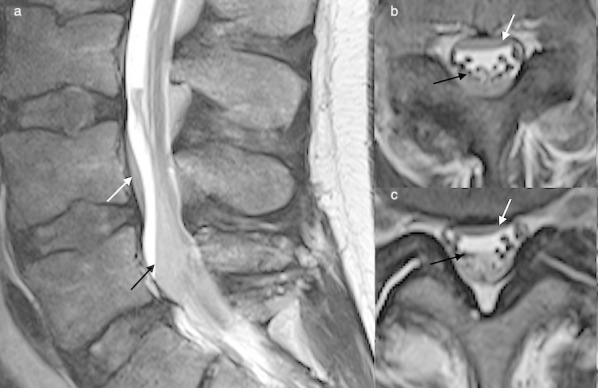

Figure 2.

Sagittal T1 (a) and T2 (b) weighted images and axial T1 (c) and T2 (d) weighted images of the lumbar spine depicting a posterior epidural haematoma (white arrows). Loss of the normal epidural fat signal in the posterior epidural space is a useful locational sign. Bulging of the dura into the canal may be seen as a smooth thin hypointense line displaced by the haematoma.

Figure 3.

T1sagittal (a) and axial (b) imaging demonstrates a right posterolateral epidural haematoma post trauma (black arrows), an associated vertebral body fracture is evident.

Figure 4.

Sagittal GRE image (a) and axial T2 weighted image (b) depicting a posterior epidural haematoma (broken white arrow) in the lumbar spine which obscures the normal epidural fat signal (solid white arrow). The dura is displaced anteriorly (black arrow). GRE, gradient echo.